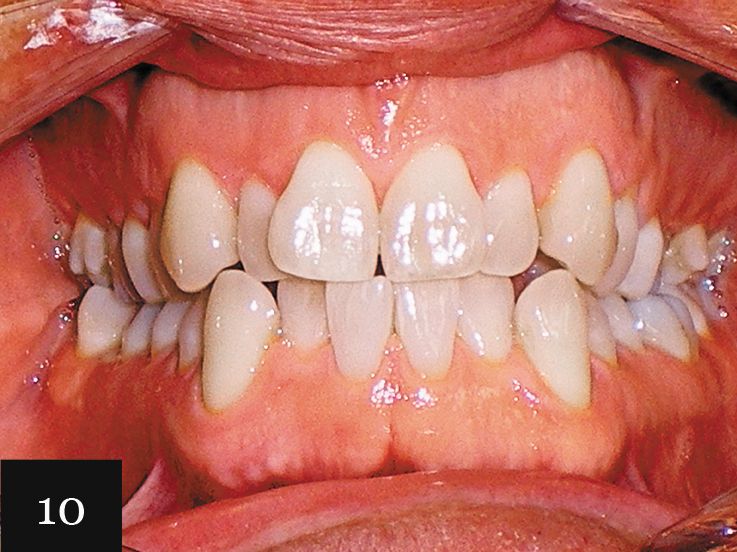

This treatment was performed on a male patient in his early 40s (Fig. 9). The patient had an omega-shaped upper arch, as seen in Fig. 10.

An impression was taken that successfully captured the complex crowding and narrow omega arch (Fig. 11), and the patient was treated with 28 aligners over 14 months. This case also illustrates use of the clear aligners as whitening trays, with the final result showing a smile that is not only straight, but also much brighter (Figs. 12-14).